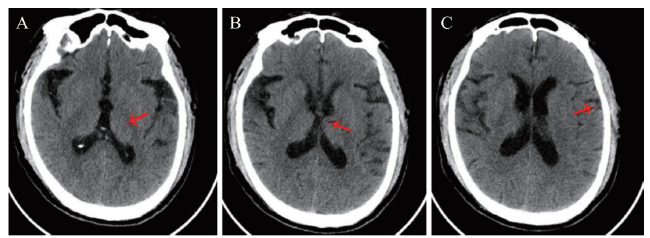

在患者入院24 h内完善相关检查。血常规:血红蛋白 155 g/L、红细胞 4.75×1012/L、白细胞 12.51×109/L、中性粒细胞0.78、血小板 189.00× 109/L。降钙素原、肝肾功能、输血前3项(获得性免疫缺陷综合征、丙型肝炎和梅毒)、抗血细胞抗体、抗核提取物抗体、免疫系列等均未见异常。脑脊液检查:腰椎穿刺测得压力190 mmH2O(1 mmH2O = 0.0098 kPa)。脑脊液:白细胞23.00×106/L,单个核细胞百分比 88.70%,多核细胞百分比11.30%;氯117.6 mmol/L,IgG 50.33 mg/L,总蛋白582.15 mg/L;脑脊液病原学检查未见明显异常。患者躁动不安,不能配合完成头颅MRI,遂立即实施头颅CT,可见左侧颞叶皮质肿胀(图1),头颅CT血管成像(CTA)未见颈部血管狭窄,头颅CTP可见左侧颞叶灌注较右侧增加(图2),排除急性脑梗死,不排除感染相关性疾病,初步考虑病毒性脑炎的可能。肥达反应+外斐反应、新型隐球菌荚膜多糖抗原检测(GXM,血清)均为(-)。动态脑电图:背景活动以7~8 Hz慢a波为主,右额颞区可见间隔0.8~2.0 s三相波、尖慢复合波呈周期性发放。重度异常脑电图(爆发-抑制)。脑脊液病原体二代测序(NGS)结果于入院后第3日回报,明确诊断为HSV-1感染所致的HSE。

图2 一例HSE患者头颅CTP

注:可见左侧颞叶、豆状核、岛叶、丘脑灌注较右侧增加(红色箭头所示)。